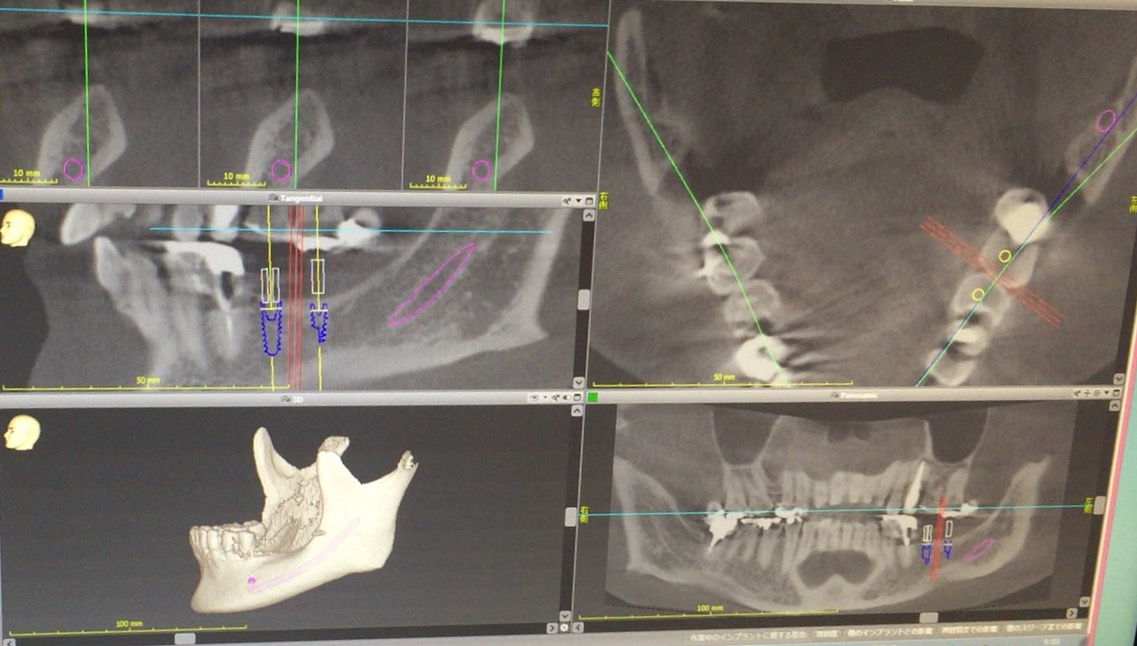

日本口腔インプラント学会に参加してきました

日本口腔インプラント学会の本大会に参加